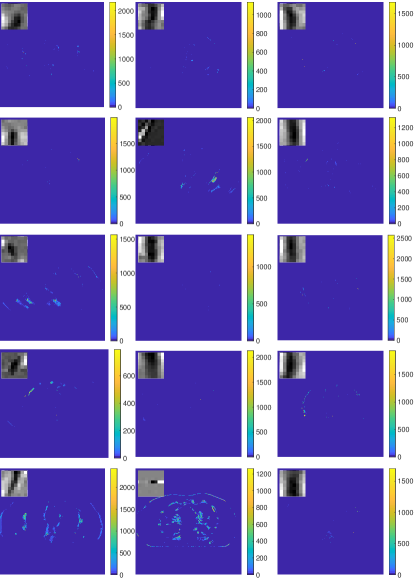

V-A2 Behavior of the learned ULTRA Models

The learned union of transforms contributes to the clustering and sparsification of image patches. To illustrate the behavior of the learned transforms, we selected 3 of the 15 transforms that capture important structures/features of the reconstructed image (with ) in their classes.

Fig. 2 (first column) shows three voxel-level classes (voxels are clustered by majority vote among patches overlapping them) for the reconstructed central axial slice. The top image only contains soft tissues, whereas the middle image shows some edges and bones in the vertical direction, and the bottom image captures some high-contrast structures. Fig. 2 (second column) shows the transforms for the corresponding classes. Each learned transform has 512 filters, and we show the first slice of 256 of these filters that show gradient-like and directional features.

VIII-B Clustering results in low-dose situations

Fig. 2 in the manuscript showed 3 out of 15 voxel-level clustering results of the reconstructed image at . Here, Fig. 13 is a binary image showing clustering memberships of all the classes for the reconstruction at . The white regions indicate pixels assigned to the corresponding class. The voxel-level clustering results (that display the pixels using their reconstructed intensities) at are actually similar to the ones shown in Fig. 2 (first column) in the manuscript. Specifically, Tab. IV shows the percentages of pixels assigned to Class 1, 13 and 14 respectively. Although is a much lower dose compared with , the clustering results only have slight changes. This illustrates that the voxel clustering based on majority vote of overlapping patches is robust in low-dose situations.